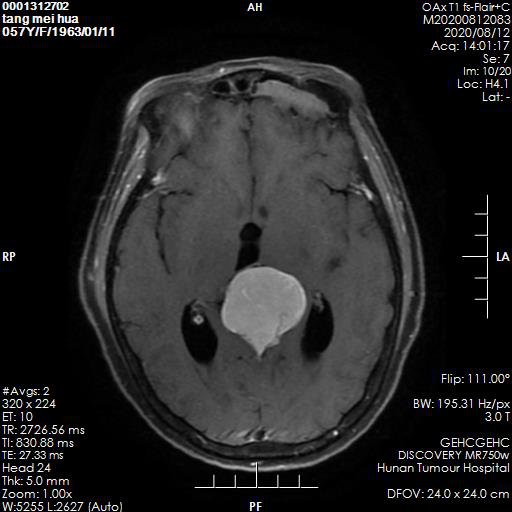

今年8月初,唐女士头痛、头昏加重,并频繁呕吐,一天可达7次,呕吐物为胃内容物,偶有胆汁,持续未见好转并日渐严重。当地医院检查发现,患者颅内松果体区占位长了一个乒乓球大小的肿瘤。

患者颅内松果体区占位长了一个乒乓球大小的肿瘤。医院 供图